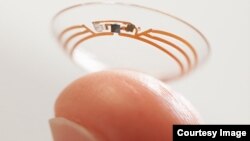

گوگل، غول دنیای اینترنت، می گوید سرگرم آزمایش یک لنز «هوشمند» است که می تواند پایین آمدن سطح قند خون افراد را به طور بصری به آنان هشدار دهد.

روی صفحه بلاگ گوگل آمده است می توان براده ها و حس گرهای بسیار ریز و آنتن های باریک تر از تار موی انسان را در موادی که برای ساخت لنزهای نرم به کار می رود جا داد. هنگامی که لنز روی عدسی چشم قرار می گیرد، می تواند در هر ثانیه یک بار میزان قند خون را به فرد اطلاع بدهد.

گوگل می گوید آزمایش های بالینی متعددی انجام داده و اکنون در حال آزمایش نمونه های اولیه با نور ال ای دی است که موقع پایین آمدن قند خون برق می زند. پژوهش گران اپلیکیشن های جدیدی را در نظر دارند که می تواند این اطلاعات را از طریق اینترنتی در اختیار پزشک و بیمار قرار دهد.